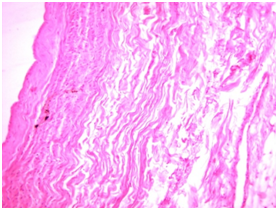

Fascia lata-during histological research was presented as a narrow plate of friable connective tissue stained with eosin evenly, with the presence of a few spindle-shaped fibroblasts with rod-shaped core. No signs of inflammation (Figure 2).

Figure 2 Spindle-shaped fibroblasts in fascia lata. Stained with hematoxylin-eosin, uv.400.